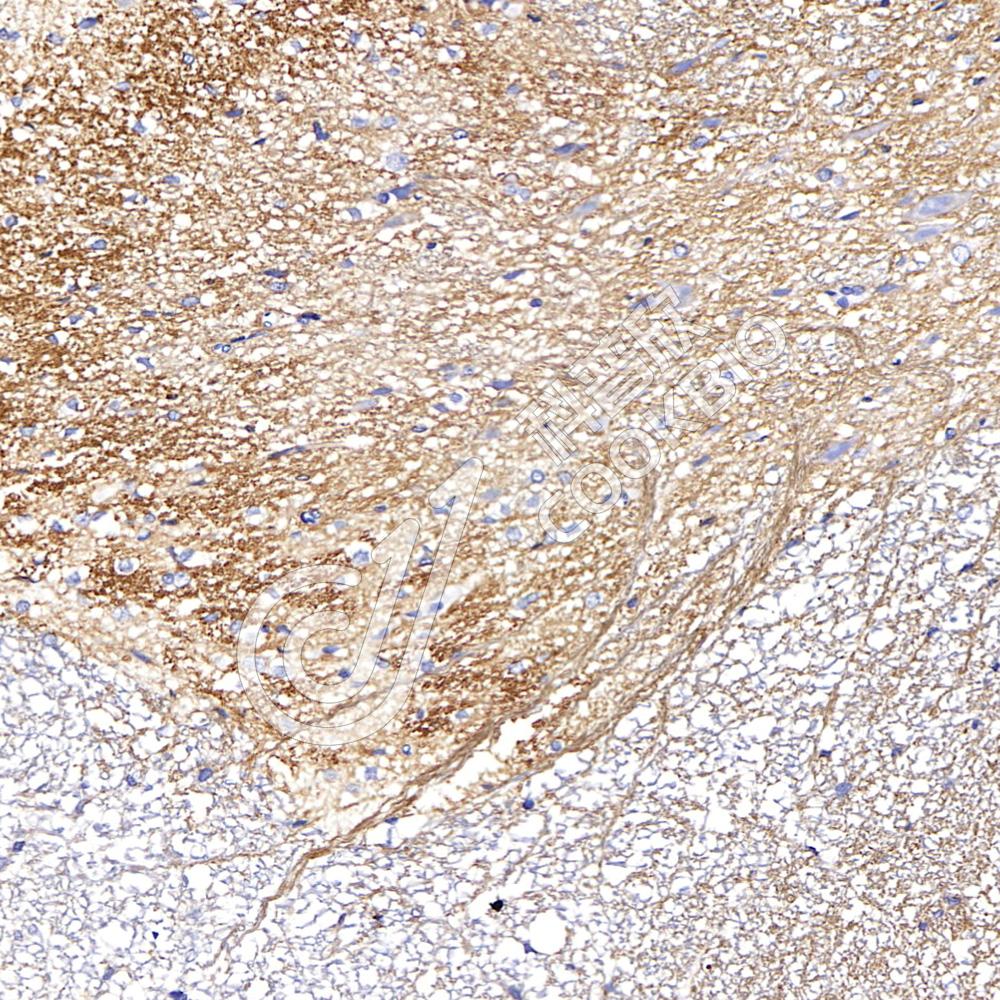

IHC检测NPY1R蛋白(货号 K1341199).

样品: 小鼠脊髓, 4%多聚甲醛 (货号KSG1101) 固定12-24小时.

抗原修复: 柠檬酸抗原修复液(干粉, pH 6.0) (KSG1201), 98℃, 20分钟.

—抗: 1: 1200稀释, 4℃ 孵育过夜.

二抗: S-vision免疫组化多聚二抗(山羊抗兔),即用型 (货号KB3906), 室温孵育20分钟.

样品: 大鼠脊髓, 4%多聚甲醛 (货号KSG1101) 固定12-24小时.